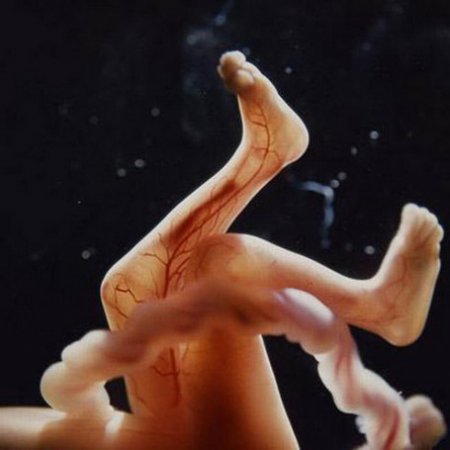

На пятой неделе продолжается интенсивное развитие плода. Формируются конечности, а также начинают развиваться глаза и уши. В этот период важно следить за своим питанием и избегать стрессов, так как это может повлиять на здоровье малыша.

На седьмой неделе беременности эмбрион уже имеет длину около 1 см. У него начинают формироваться пальцы на руках и ногах, а также развиваются внутренние органы. Важно продолжать вести здоровый образ жизни и избегать вредных привычек.

Пятая неделя беременности характеризуется формированием плаценты, являющейся источником кислорода и питательных веществ будущего человечка. Начинают формироваться уши и глаза ребёнка, появляются отростки пальчиков.

Длина эмбриона к концу пятой недели беременности составляет 6,5 мм. Также на этой неделе начинают формироваться зачатки сердечно-сосудистной системы ребнка, которые будут заканчивать свое развитие еще несколько недель